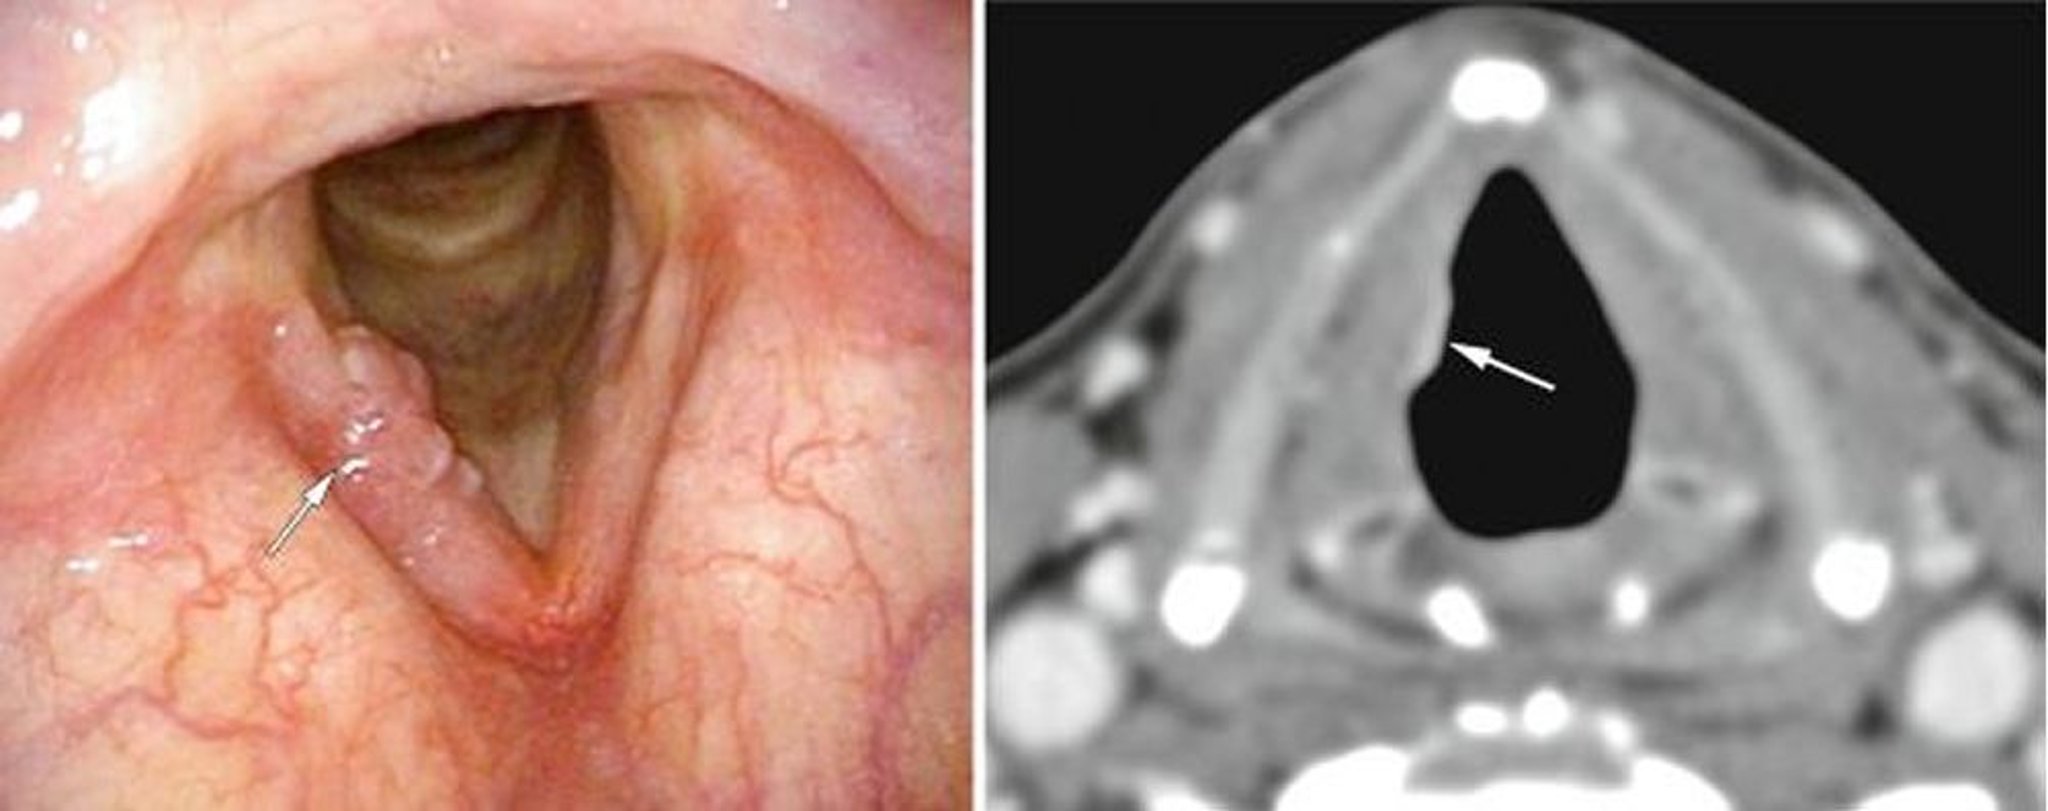

Tumore della laringe allo stadio iniziale

Questo paziente ha avuto un cancro della laringe glottico precoce, qui visibile su una corda vocale all'endoscopia (immagine a sinistra, freccia bianca) come escrescenze, e alla TC (immagine a destra, freccia bianca) come un'anomala densità dei tessuti molli.